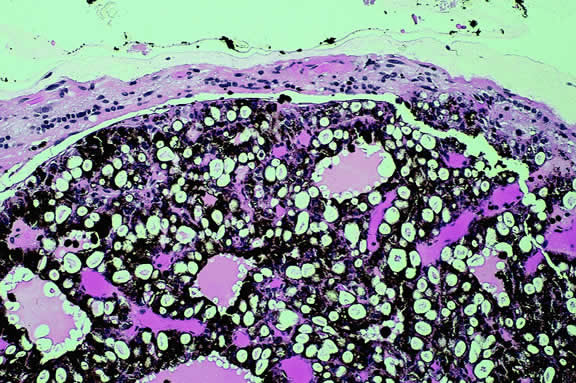

Nevi constitute the benign end of the biologic spectrum of melanocytic neoplasms. Most nevi are bland spindle cells tumors. Histopathologically, the choroidal stroma typically is replaced by a compact infiltrate of slender pigmented or nonpigmented spindle cells (Fig. 2). The nevus cells have bland oval or cigar-shaped nuclei that have finely dispersed chromatin and lack nucleoli or nuclear folds. Intranuclear cytoplasmic inclusions are common in some cases. Mitotic activity is absent. In some cases, the nevus cells are plump and dendritic in shape.9 Foamy balloon cells that appear to be undergoing lipoidal degeneration are found in 4% of nevi.4 Maximally pigmented, plump, polyhedral nevus cells comprise the magnocellular variant of nevus called melanocytoma (see later).

Fig. 2. Choroidal nevus. Choroidal stroma contains an infiltrate of pigmented spindle cells with bland nuclei. The retinal pigment epithelium is intact and the overlying retina remains attached. (Hematoxylin-eosin, × 100.)